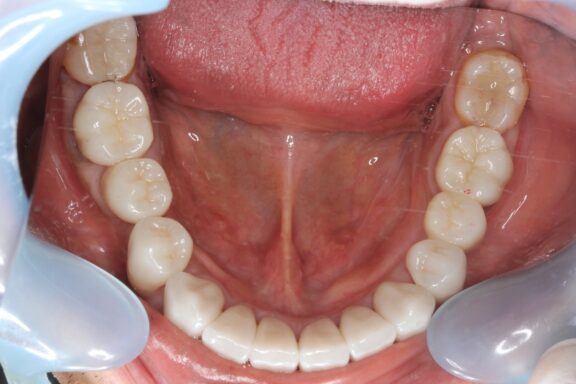

完成がこちらになります。

必要箇所には顕微鏡(マイクロスコープ)にて根管治療を行い、先月、全部の治療が完成しました。

術前、術後で比較すると、とても口腔内が明るくなり、正面から見てもとても若々しく感じます

今回は約1年ほどかけながら順番にゆっくり焦らずしっかりと治療を行っていきました。